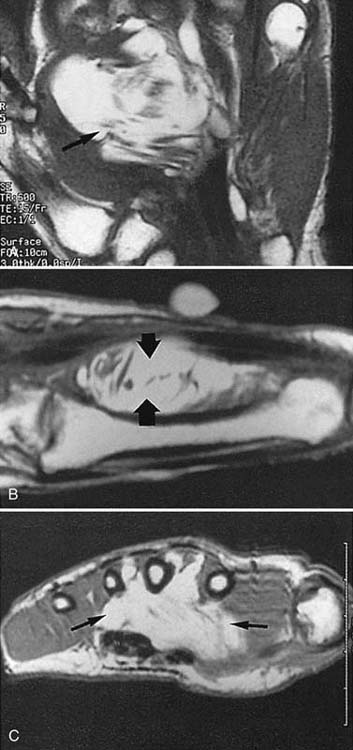

MRI is of great value in defining soft tissue abnormalities (Figs. 13-17 to 13-19, all online). In the evaluation of tumors, it cannot provide a specific diagnosis, but it can define the size of the lesion and the extent of involvement of marrow and neurovascular structures (Fig. 13-20, online).27 Other soft tissue abnormalities diagnosed more easily by MRI include ganglions, ligament tears, and cartilage abnormalities (Fig. 13-21).28,29 Dorsal wrist pain can be attributed to hypertrophy of the dorsal capsule as well as ganglions that may be occult and not palpable. Patients with dorsal wrist pain of unknown origin are therefore candidates for MRI evaluation. MRI is especially helpful in diagnosing tears of the scapholunate and lunotriquetral ligaments, particularly when dissociation of the scapholunate is not evident on plain films.30 Excellent depiction of the TFC can be achieved with MRI, but the image must be interpreted carefully; thinning of the disk occurs in many patients, but a tear of this structure is not diagnosed unless an avulsion from the ulnar or radial insertion can be observed.31-33

images

Figure 13-17 Synovial sarcoma. A, Sagittal magnetic resonance image showing a soft tissue mass (arrow). The white object (curved arrow) is a marker (raw almond) placed over the palpable mass (straight arrow). B, Axial magnetic resonance image obtained after contrast enhancement demonstrates the mass again (arrows) and shows that the neurovascular bundle is encased by tumor.

Figure 13-18 Infiltrating lipoma of the palm. Magnetic resonance images of the sagittal (A), coronal (B), and axial (C) planes show the extent of the lesion (arrows).

Figure 13-19 Hemangioma. Axial magnetic resonance images through the palm show a mass between the third and fourth metacarpals (arrow). MRI is capable of depicting the extent of a soft tissue mass but cannot provide a specific pathologic diagnosis. A contrast arteriogram of this hand is shown in Figure 13-15.

Figure 13-20 Aneurysmal bone cyst. This magnetic resonance image reveals an abnormality at the base of the second metacarpal. The fluid-filled level (arrow) is a typical finding in such cases.

Figure 13-21 Ganglion. A, This axial magnetic resonance image demonstrates a dorsal mass (arrow) that was not palpable on clinical examination. B, Coronal magnetic resonance image in another patient showing a mass in the abductor canal (arrow).